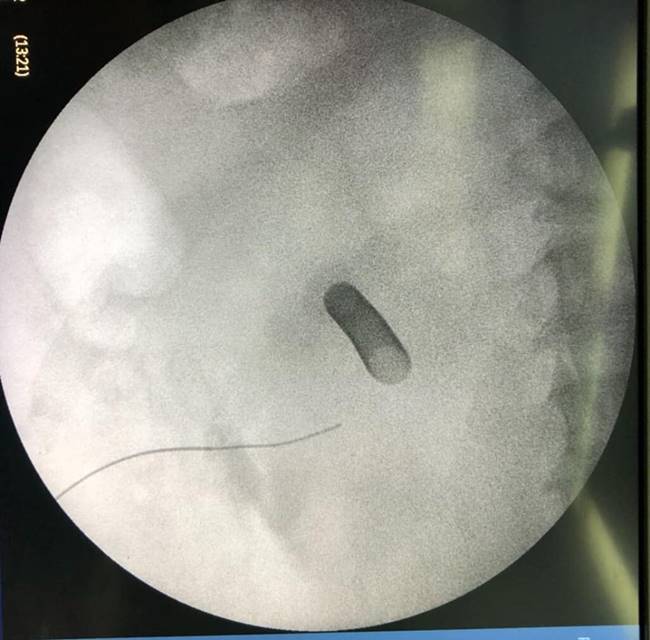

หมอเผยภาพสุดน่ากลัว ผ่าตัดนิ่วจากไตคนไข้ พบมีจำนวนมากจนสามารถเรียกต่อเป็นคำว่า "นิ่ว" ได้ แนะคนไม่อยากเป็นโปรดดื่มน้ำวันละ 6-8 แก้วต่อวัน

เผยภาพนิ่วจำนวนมาก

หลังผ่าตัดออกมาจากร่างกายของคนไข้ที่มีอาการปวดหลังเรื้อรัง

พบว่ามีจำนวนมาก จนสามารถนำมาเรียงต่อกันได้คำว่า "นิ่ว"

พร้อมกันนี้ คุณหมอได้ระบุข้อความว่า "ของกลางที่พบในคนไข้รายหนึ่ง หลังจากที่ต้องทนทุกข์ทรมานกับอาการปวดหลังและอาการไตเสื่อม คงไม่ต้องบอกว่า......คืออะไร

ขอบคุณโครงการ #ก้าวคนละก้าว ที่นำเครื่องมือผ่าตัดนิ่ว มาสู่รพ.ยะลา

Uro Yala Team"